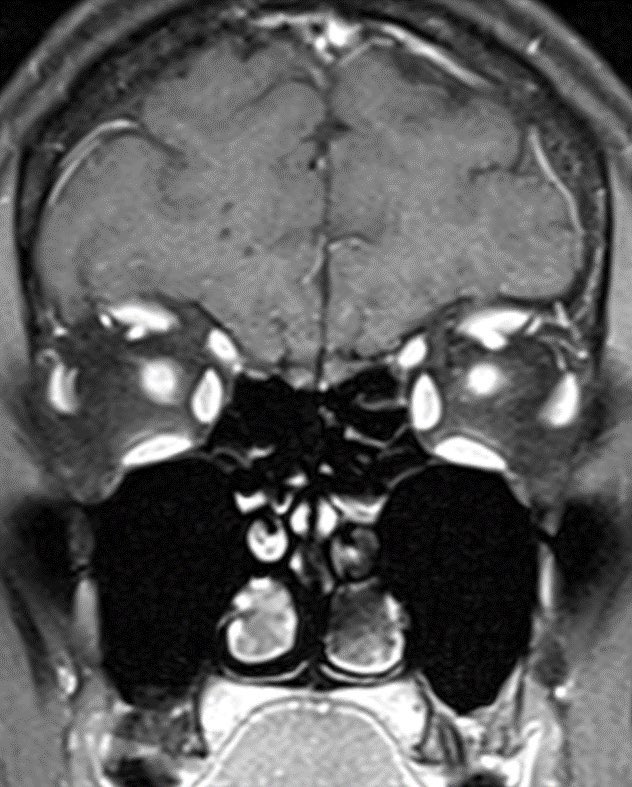

Answer: FUEL “FLAIR-variable unilateral enhancement of the leptomeninges” in MOGAD

🔷A distinct subtype/clinicoradiographic syndrome of MOGAD is a cortical encephalitis presenting with headache, fever and seizures known as FLAMES of MOGAD🔥

🔷When the predominant imaging features are leptomeningeal enhancement with little to no cortical involvement, this is considered FUEL of MOGAD ⛽️ x.com

🔷FUEL ⛽️& FLAMES 🔥

▶️Imaging: Unilateral (more common) or b/l cortical swelling (🔥) or isolated leptomeningeal enhancement (⛽️) +/- other features of MOGAD